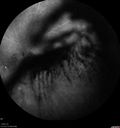

74 year old man with diabetes for about 40 years. No previous problems or treatments: EXTENDED HPI: Starting a little less then a week ago he woke up with something in the left eye. He saw a big blob in his vision. Since it started it is not getting better (also not getting any worse). The right eye is OK. This has not happened before. He is on ASA and Clopidogrel. VA OD: sc20/20+2 NscJ7-1 VA OS: sc20/63-2 NscJ2

Vitreous Hemorrhage with no evidence of PDR in the left eye418 views74 year old man with vision loss OS for about a week. The FA shows no PDR in the left eye but the right eye has very mild NVD. Diabetes for 40 years now on insulin.00000